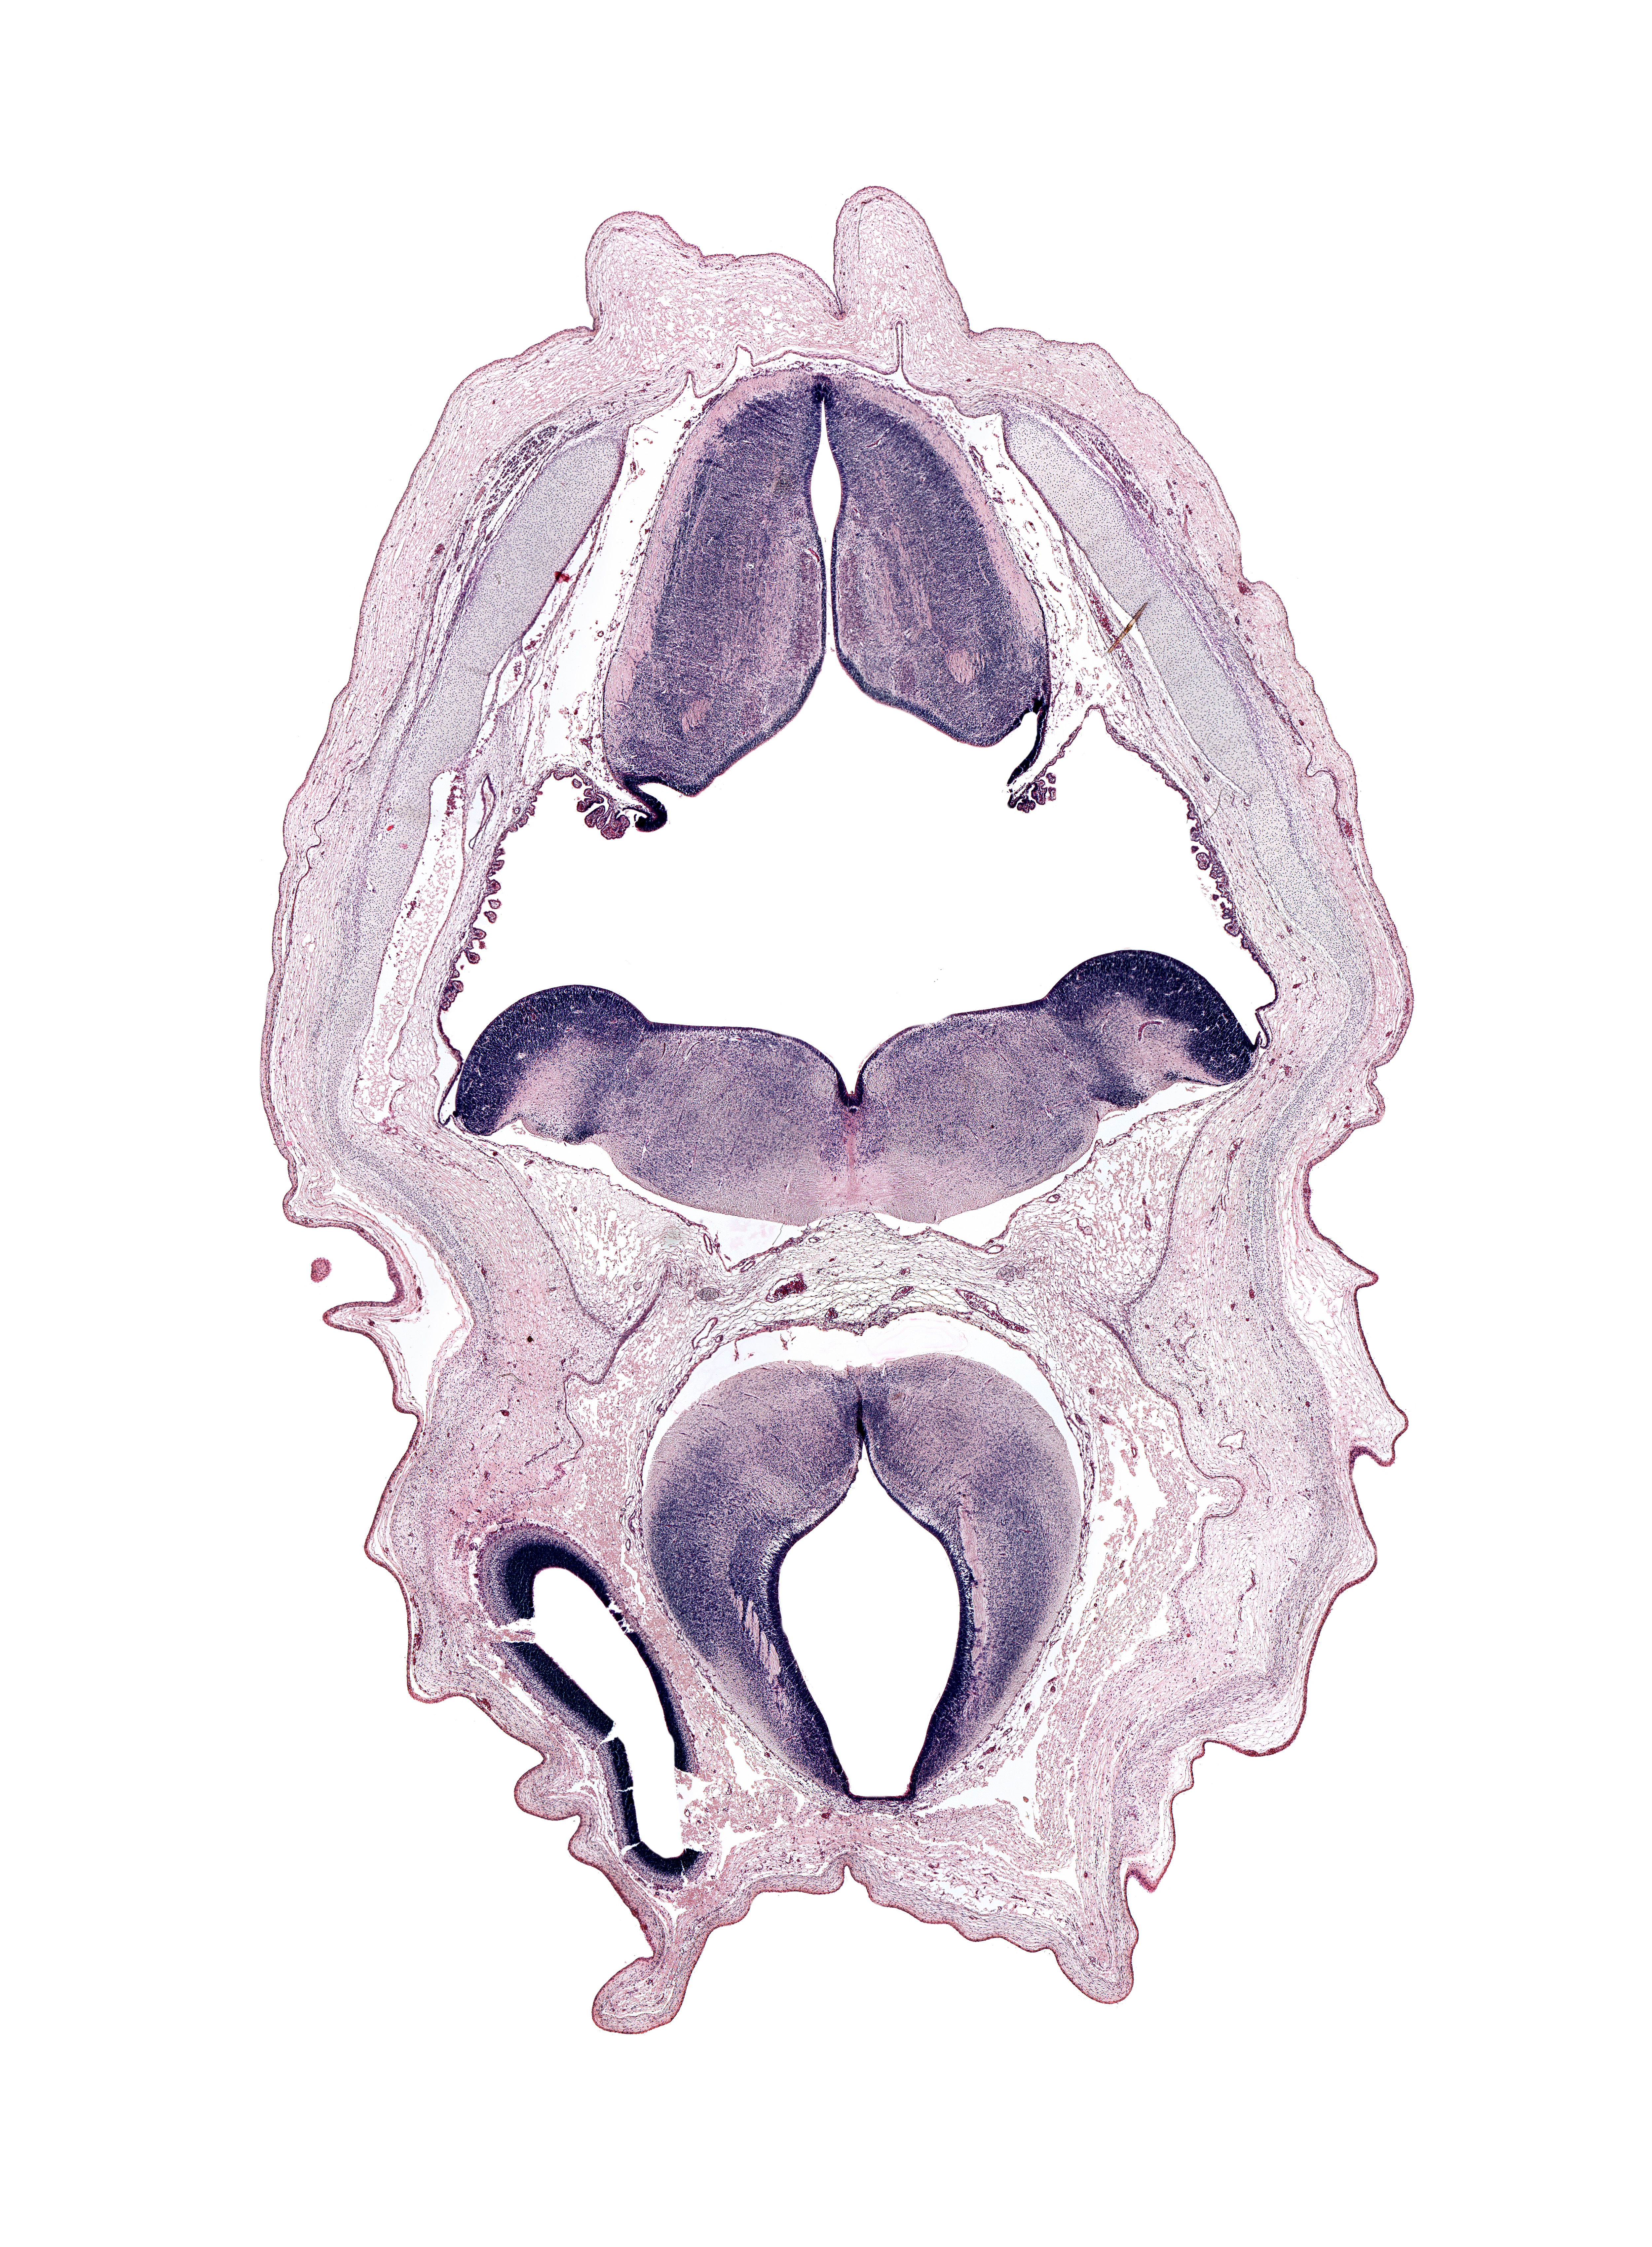

Boyd Embryo #H983 | Location: 35-1-2

Keywords: alar plate of metencephalon (cerebellum), artifact space(s), cerebral vesicle (hemisphere), cochlear nucleus area, diencephalon, fiber tract, hypoglossal nucleus, median sulcus, obex, pons region (metencephalon), posterior cerebral artery, rhombencoel (fourth ventricle), subarachnoid space, sulcus limitans, tegmentum of mesencephalon, tegmentum of metencephalon, tractus solitarius

Source: The Virtual Human Embryo.